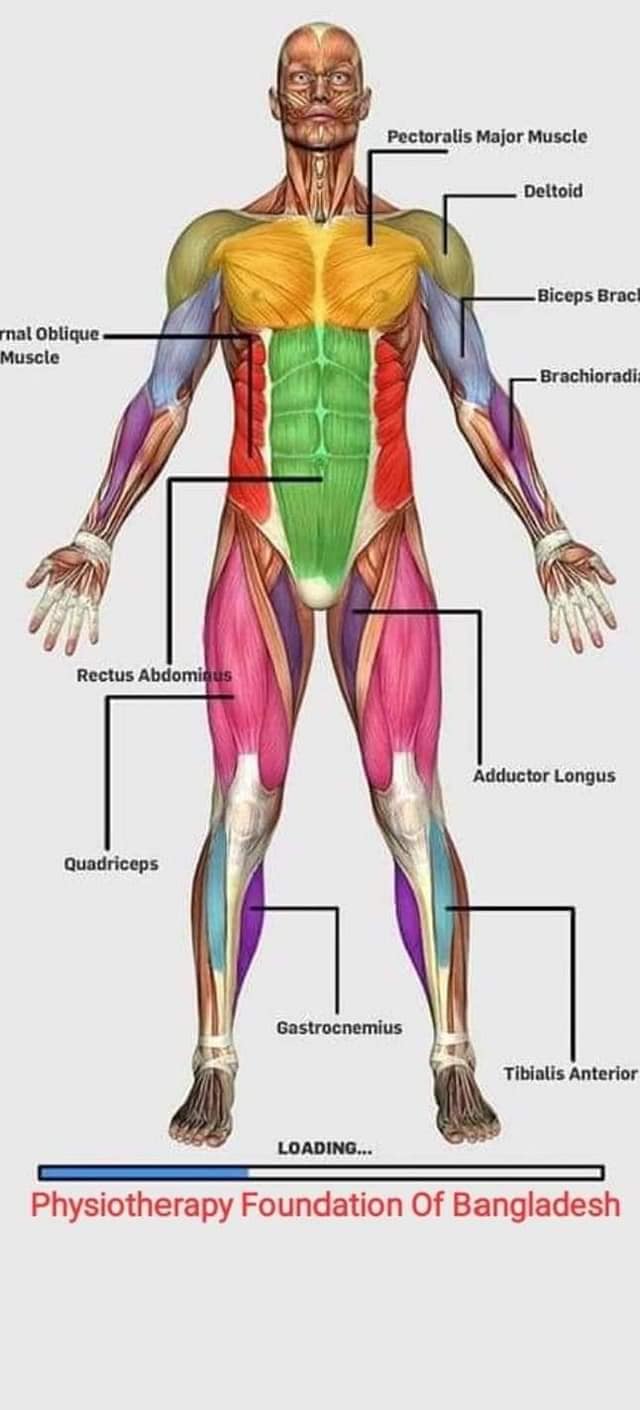

Скелетно-м'язова система людини (синоніми: Опорно-рухова система, опорно-руховий апарат, кістково-м'язова система, локомоторна система) — комплекс структур який утворює каркас, надає форму організму, дає йому опору та забезпечує захист внутрішніх органів і можливість пересування у просторі. Це функціональна сукупність кісток скелета, їх з'єднань (суглобів і сінартрозів), і соматичної мускулатури з допоміжними пристосуваннями, які здійснюють за допомогою нервової регуляції локомоції, підтримання пози, міміки та інших рухових діях, поряд з іншими системами органів утворює людське тіло.

Це саморушний механізм, який складається з 400 м'язів, 206 кісток і декількох сотень сухожиль. Більшість кісток скелету з'єднане рухомо за допомогою суглобів. Одним кінцем м'яз прикріплюється до однієї кістки, утворюючи суглоб, іншим кінцем — до іншої кістки. В англомовній літературі застосовують близькі за значенням терміни: англ. musculoskeletal system (скелетно-м'язова система) та англ. locomotor system (локомоторна система).

М'язова система людини є однією з основних систем організму, що відповідає за рухи, підтримання пози та стабільність. Вона складається з понад 600 м'язів, які можна класифікувати на скелетні, гладкі та серцеві м'язи. Скелетні м'язи, які є об'єктом нашого детального розгляду, дозволяють контролювати навколишній світ і виконувати різноманітні рухи. Особливу увагу в нашій статті буде приділено шейним і спинним м'язам, оскільки ці групи м'язів мають критичне значення для підтримання правильного постава та функціонування хребта.

Скелетні м'язи з'єднані з кістками за допомогою сухожиль і відповідають за більшість волевих рухів. Вони поділяються на:

- Швидкі м'язи - призначені для швидких і потужних рухів.

- Повільні м'язи - забезпечують стійкі і довготривалі рухи.

Скелетні м'язи мають поперечну смугасту структуру, що забезпечує їхню здатність до швидкого і ефективного скорочення.